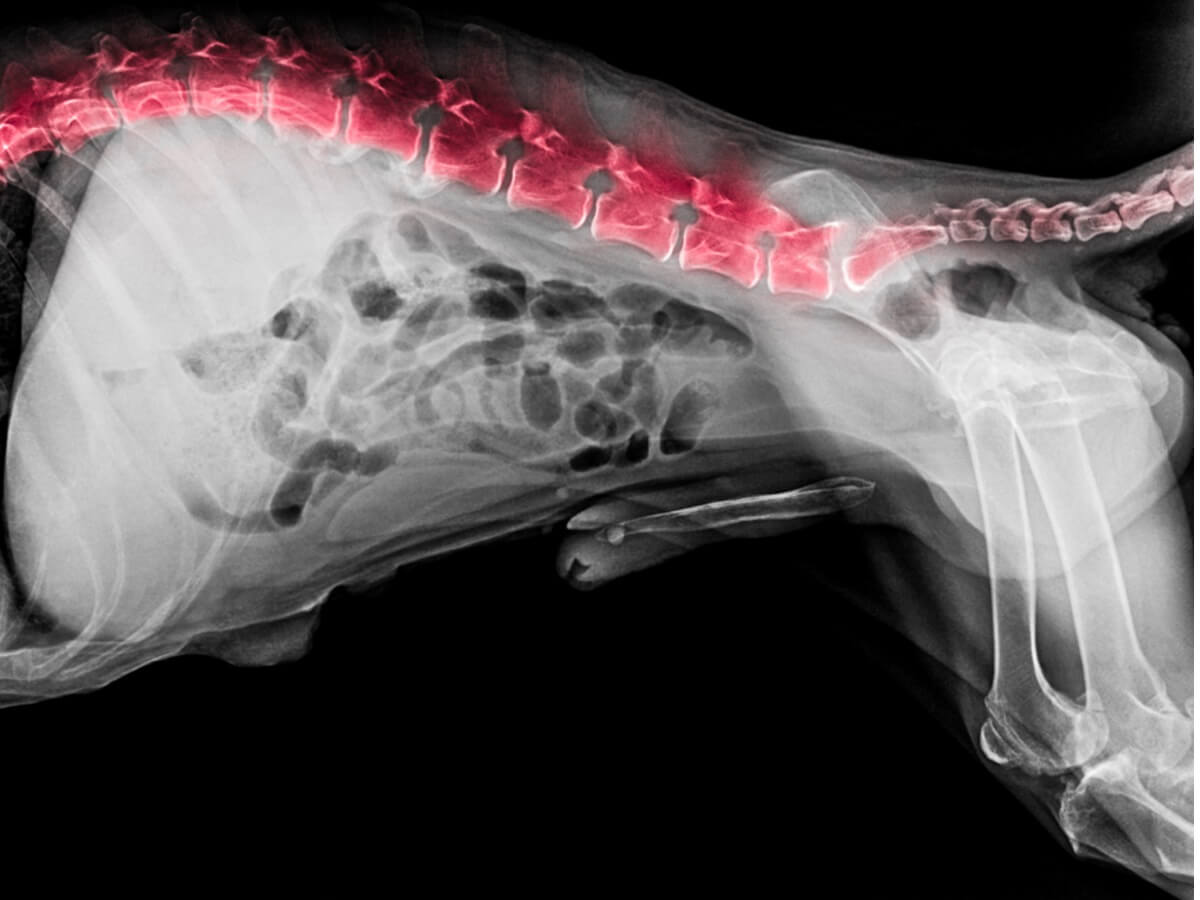

A esto se añade un examen radiológico (con rayos X) que permite la observación del estado de las vértebras. Mediante esta radiografía se determina si existe espondilitis anquilosante, hernia, desgaste de los discos intervertebrales, infecciones, tumores u otras dolencias.

En el caso de los perros, el dolor se localiza en las 3 últimas vértebras lumbares (L5-L6-L7) y el hueso sacro, que conecta la pelvis con la columna vertebral. Además de afectar a los huesos, la lumbalgia aumenta el tono muscular en la zona, causando dolor y rigidez a nivel locomotor.